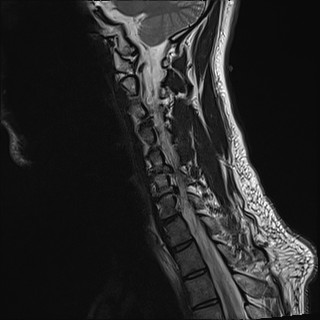

Wirbelsäule HWS

t2_tse_sag